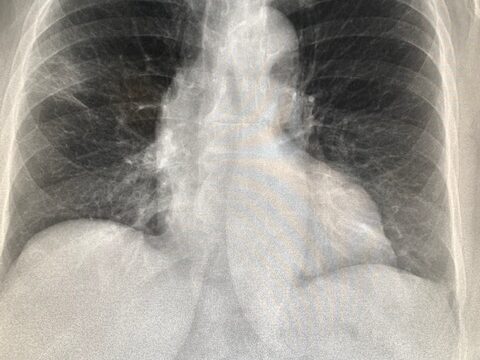

Më shumë gra në Zvicër po vdesin nga kanceri i mushkërive

Kanceri i mushkërive dikur konsiderohej kryesisht një sëmundje mashkullore, por sot ai është shkaku i dytë më i shpeshtë i vdekjes tek gratë. Kjo ndodh pjesërisht për shkak se duhanpirësit sot thithin më thellë, dhe pjesërisht për shkak të hormoneve që rrisin rrezikun e zhvillimit të kancerit të mushkërive tek gratë.

Historikisht, kanceri i mushkërive ishte më i përhapur tek meshkujt, pasi ata pinin më shumë dhe ekspozoheshin më shpesh ndaj ndotjes së ajrit ose substancave të tjera kancerogjene në punë. Por tani, situata po ndryshon: në Gjermani, për herë të parë këtë vit, kanceri i mushkërive ka tejkaluar kancerin e gjirit si shkak i vdekjes tek gratë.

Edhe në Zvicër numrat po rriten ndjeshëm. Sipas të dhënave të fundit të Zyrës Federale të Shëndetit Publik (BAG), midis viteve 2018 dhe 2022, 1,364 gra vdiqën nga kanceri i mushkërive – vetëm gjashtë më pak se nga kanceri i gjirit. Për më tepër, numri i grave që vdesin nga kanceri i mushkërive është më shumë se dyfishuar që nga vitet 1990.